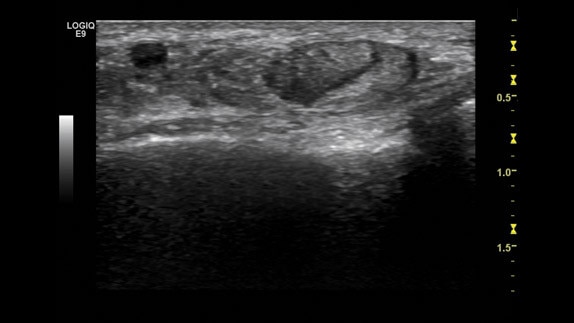

Hemorajik kist, RSP6-16 probu